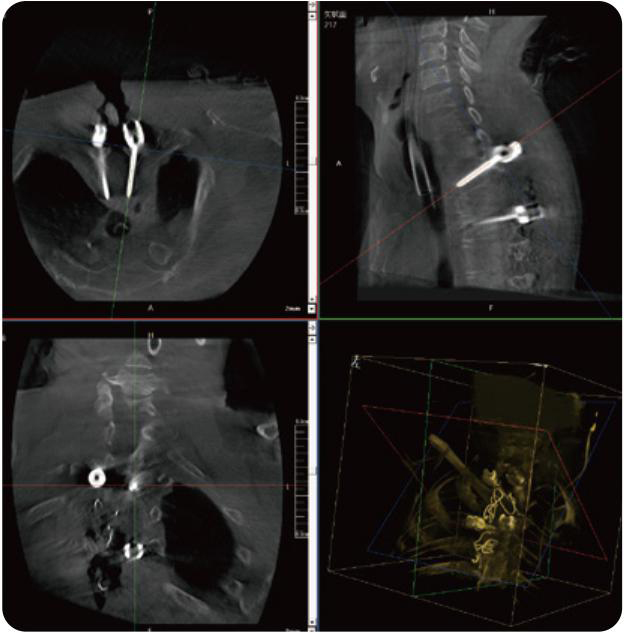

PL300B可應(yīng)用于多節(jié)段脊柱外科手術(shù),輔助醫(yī)生定位病灶部位,為脊柱外科手術(shù)(經(jīng)皮椎體成形術(shù)、椎弓根螺釘內(nèi)固定術(shù)等術(shù)式)提供術(shù)前手術(shù)流程規(guī)劃、入釘位置、角度可視化引導(dǎo),模擬仿真入釘輔助。

PL300B搭配普愛(ài)醫(yī)療自主研發(fā)生產(chǎn)的平板3D C形臂,借助一體化自適應(yīng)配準(zhǔn)( 軌跡配準(zhǔn))技術(shù),通過(guò)追蹤C(jī)形臂三維采集軌跡,自動(dòng)完成圖像坐標(biāo)建立和系統(tǒng)坐標(biāo)配準(zhǔn)。配準(zhǔn)精度更高,操作步驟少,系統(tǒng)運(yùn)作效率高。